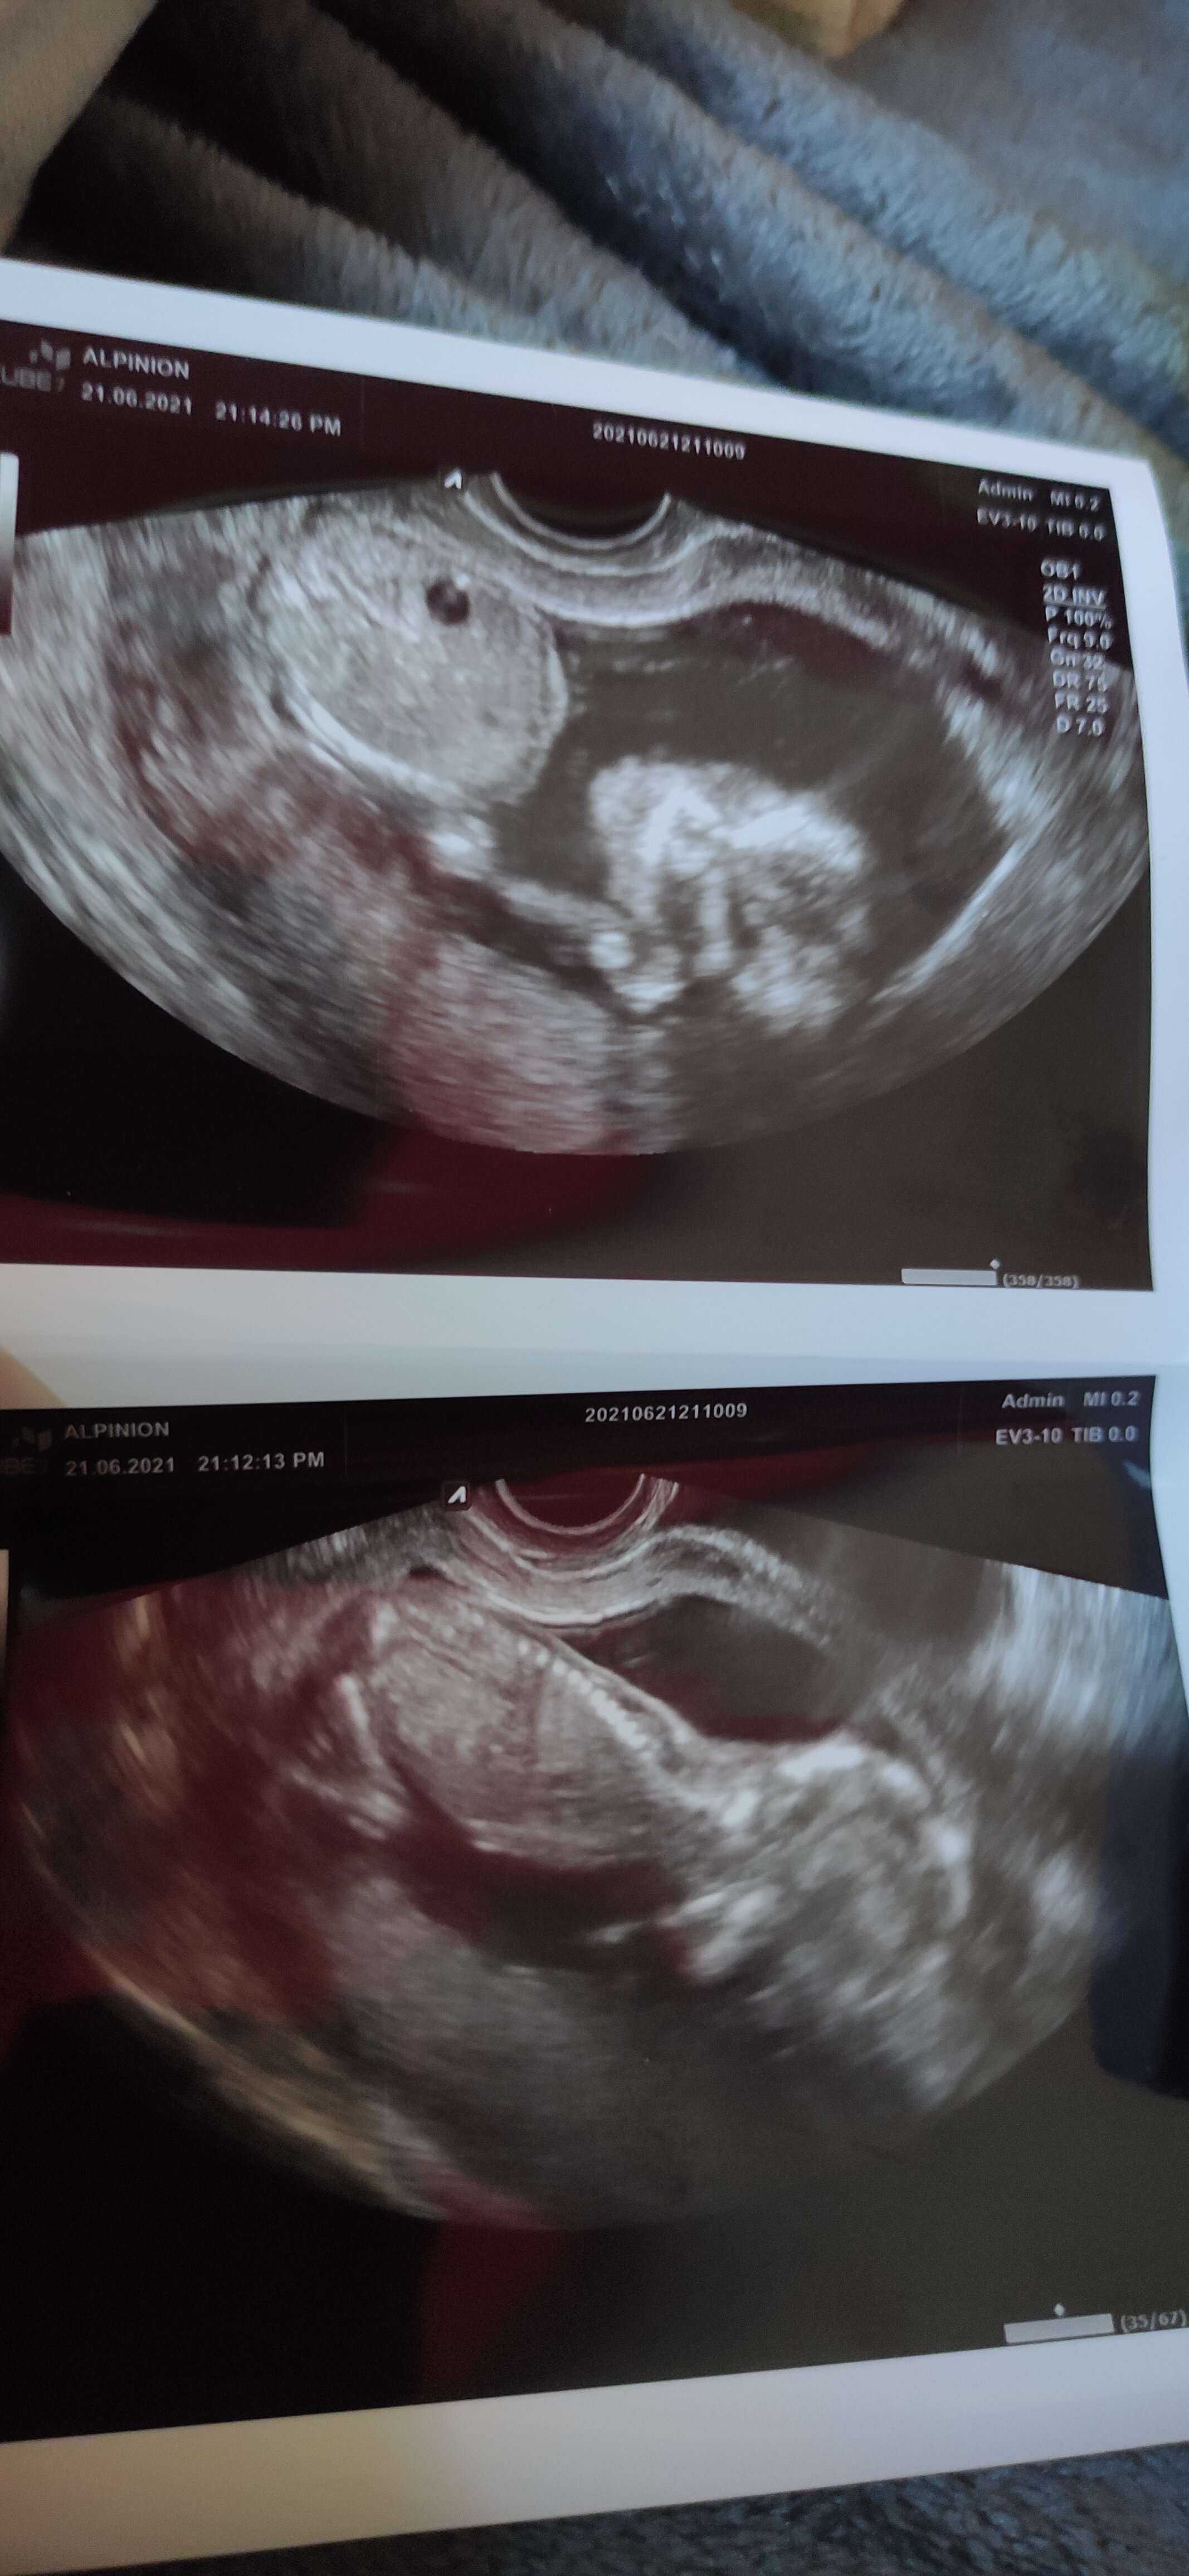

Oszalałam na badaniach plenatarnych 90% dziewczynka dosłownie tydzień temu . Teraz na wizycie 60 % chłopak 😂 któraś z was miała już taką sytuację ?

Załączniki

• IMG_20210621_182847.jpg

IMG_20210621_182847.jpg

1,1 MB · Wyświetleń: 142